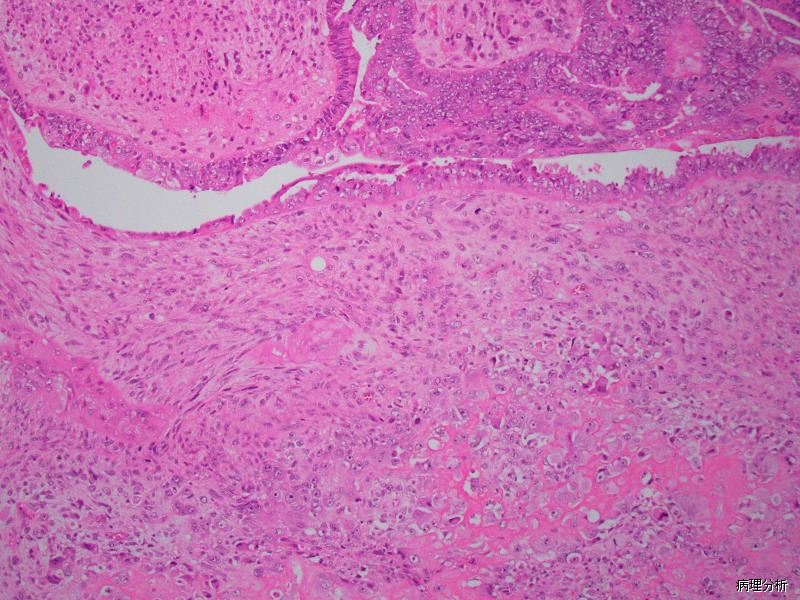

双向分化肿瘤,由高级别癌和肉瘤两种成分构成。

组织学上由恶性的上皮成分和恶性间叶成分混合组成;

上皮成分表现多样,浆液性癌、子宫内膜样癌和高级别非特殊性癌是最常见的癌成分,透明细胞癌、黏液性癌、鳞状细胞癌和中肾管癌也可作为上皮性成分,但不常见;

大约一半病例具同源性间叶成分,其中大多数病例为高级别梭形细胞肉瘤或多形性肉瘤,极少病例类似于平滑肌肉瘤或子宫内膜间质肉瘤;

异源性间叶成分以横纹肌肉瘤和软骨肉瘤最常见;

出血坏死常见;

常见脉管侵犯;